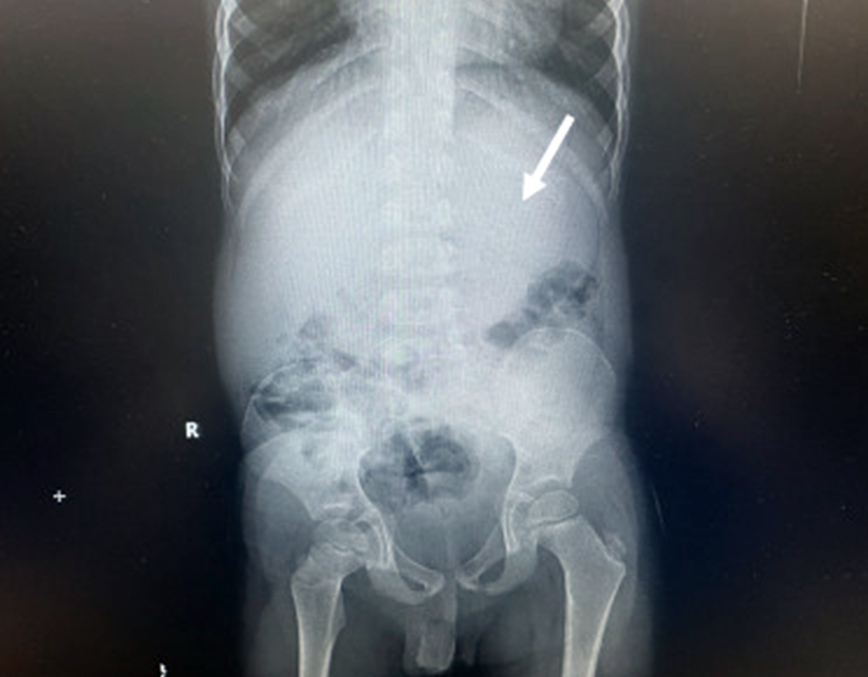

Η ομάδα των γιατρών, με επικεφαλής τον Dr. Chizite Iheonunekwu της Cleveland Clinic, ανακάλυψε το περιεχόμενο στην κοιλιά του με ακτονογραφίες, οι οποίες αποκάλυψαν τη μεγάλη μάζα.